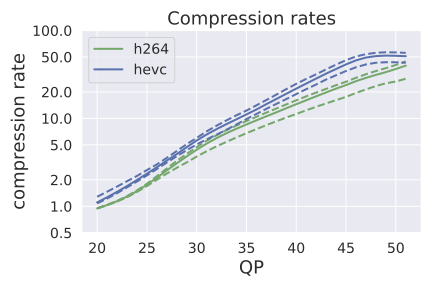

Compression rates: Figure 1 (left) shows the distribution of compression rates on colonoscopy videos for H264 and HEVC by QP value. At QP 51 (the highest compression rate for both classical codecs), HEVC achieved significantly more compression: the 25th, 50th, and 75th percentile compression rates were (43.6, 51.8, 56.5) for HEVC and (28.3, 39.8, 44.5) for H264.